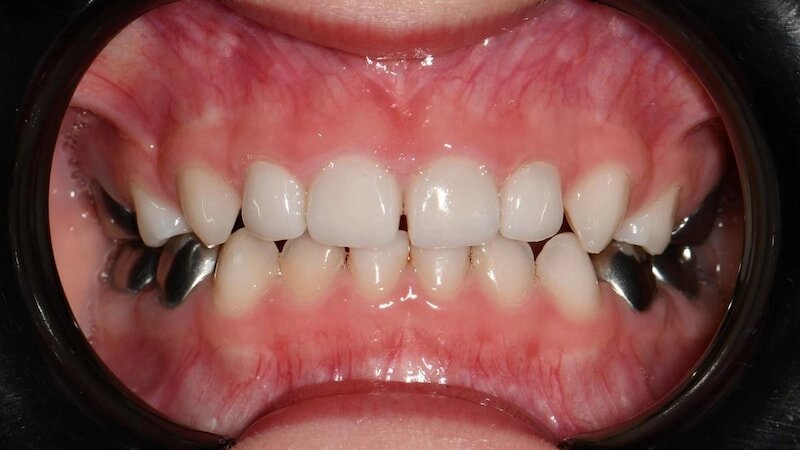

Так выглядят зубы, которые восстановили циркониевыми коронками, спустя 2 года после лечения:

-15